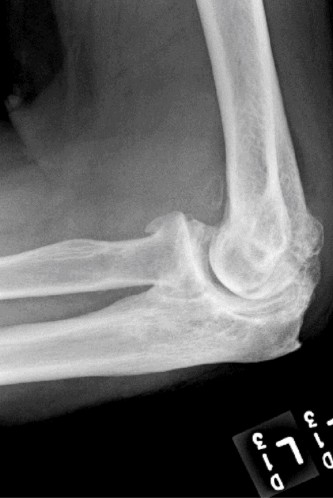

Treat a patient with infected total shoulder arthroplasty? CASE 21 A 70-year-old, right-hand-dominant female presents to clinic complaining of 4 years of gradually worsening chronic right shoulder pain and stiffness. She says the pain is worse at night and with any range of motion, denies a history of trauma, pain in other extremities, or numbness or tingling of the right upper extremity. She notes that her mother suffered from rheumatoid arthritis that affected her shoulder. Physical examination reveals decreased muscle bulk over the right supra- and infraspinatus fossae compared to the contralateral side, limited active and passive ROM, marked weakness with external rotation, and 4+/5 strength with shoulder abduction. X-rays of the right shoulder are shown in Figures 2–58 and 2–59.

Figure 2–58

Figure 2–59

The correct answer is (C). Rotator cuff tear arthropathy consists of a combination of rotator cuff insufficiency, glenohumeral joint degenerative changes, and superior humeral head migration. It is more common in women and also more often found on the dominant side. The patient’s clinical examination with weakened external

rotation and muscle atrophy signaling incompetent supra- and infraspinatus muscles point to rotator cuff insufficiency, and her plain films reveal narrowed glenohumeral joint space as well as superior migration of the humeral head. Choice D is incorrect because, while radiographs would show narrowing of the glenohumeral joint space, they would also likely show numerous osteophytes and posterior wear of the glenoid. Choice B is incorrect because, while adhesive capsulitis does present as decreased active and passive range of motion, the patient’s constellation of symptoms pointing towards rotator cuff insufficiency along with the radiographs make cuff tear arthropathy the more likely choice. Finally, Choice A is incorrect because even though she has a positive family history of rheumatoid arthritis, it is less likely to present only in a single joint. Also, rheumatoid arthritis on radiography appears more as an erosive process without the characteristic superior migration of the humeral head.

The correct answer is (A). Superior migration of the humeral head would be most indicative of chronic rotator cuff insufficiency associated with cuff tear arthropathy, as it is a direct result of the inability of the rotator cuff tendons to help maintain the humerus in its normal position. Acetabularization of the undersurface of the acromion is commonly associated with superior migration of the humeral head found in rotator cuff tear arthropathy, and can be assessed using the Hamada classification, which is based on measurements of the acromiohumeral interval on radiography (Table 2–8). Choices B and C are incorrect because, while narrowed glenohumeral joint space and subchondral sclerosis are associated with rotator cuff arthropathy on radiographs, they indicate degenerative joint changes rather than chronic rotator cuff insufficiency. Choice D is incorrect because it is not a specific sign of rotator cuff arthropathy.